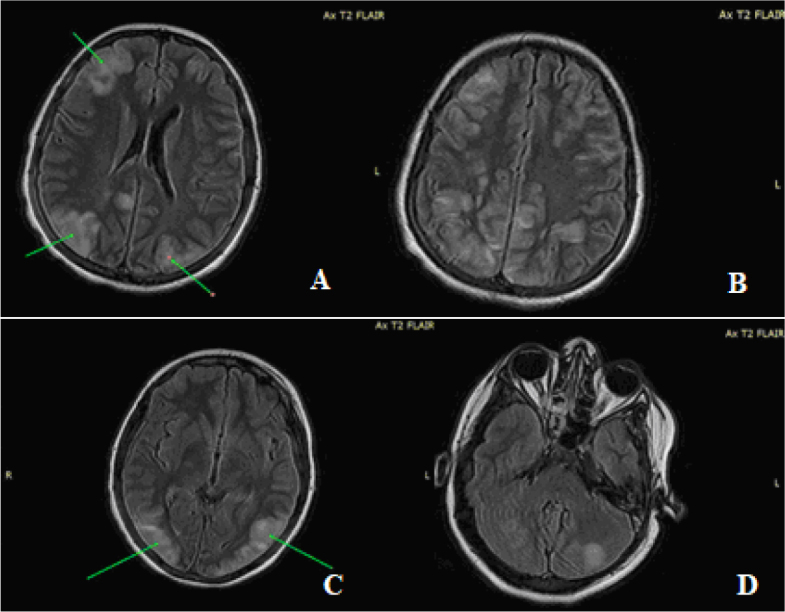

Presentation of case series: In the past six months, we have documented the cases of two patients, aged 15 and 10, both of whom presented with PRES and renal disease. These patients were admitted because of general malaise, headaches, nausea, vomiting, visual disturbances, and elevated blood pressure. Subsequently, both patients experienced epileptic episodes. Only the first patient required transfer to the Pediatric Intensive Care Unit (PICU). Cerebral magnetic resonance imaging (MRI) scans revealed distinct PRES lesions in both cases. Following comprehensive investigations, both cases were diagnosed with PRES in the context of acute post-streptococcal glomerulonephritis.